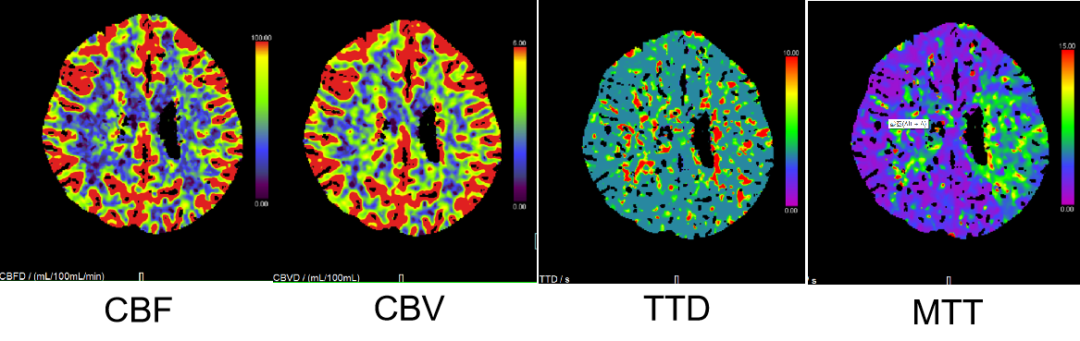

CTP:左侧大脑半球低灌注。

2、CTP 低灌注I期:代偿期

2、左侧大脑半球低灌注